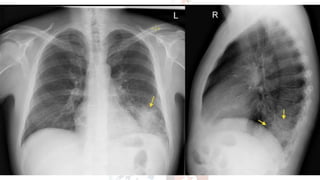

CHEST X RAY (CXR) Check for..

A – airways

B – basal lungs & pleura

C – cardio mediastinum

D – disabilities (visible fractures etc)

E – everything else

• R > L diaphragm gap (not more than 3cm)

• Cardiothoracic ratio not more than <55%

• Trachea diameter < 25mm in males/ < 21mm in females.

• Aortic notch should be visible.

• Any gastric abnormalities (bubbles)

CHEST X RAY(CXR) Check for.. A – airways B – basal lungs & pleura C – cardio mediastinum D – disabilities (visible fractures etc) E – everything else • R > L diaphragm gap (not more than 3cm) • Cardiothoracic ratio not more than <55% • Trachea diameter < 25mm in males/ < 21mm in females. • Aortic notch should be visible. • Any gastric abnormalities (bubbles)